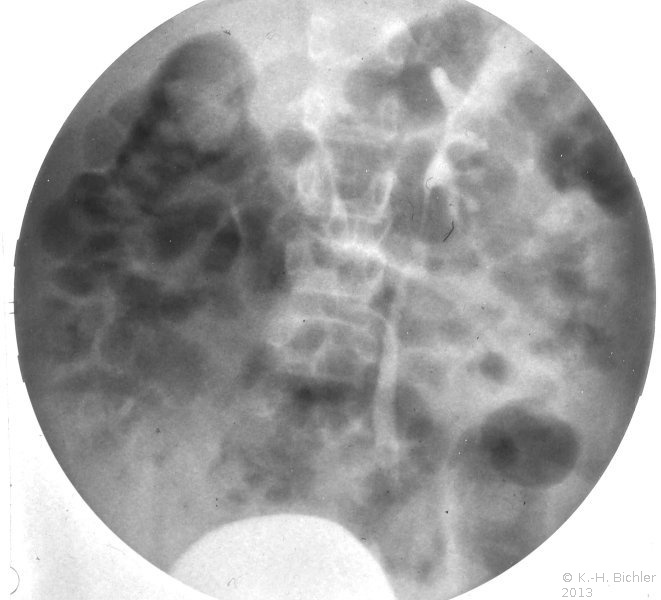

Die Abbildungen zeigen die Anwendung von Sonographie und Miktionszysturethrogramm bei einer kleinen stummen Niere (Abbildung 13, 14).

Neben der Anamnese, körperlicher Untersuchung, Messung des Blutdruckes sowie der Laboruntersuchungen: Urinstatus, Serumkreatinin und -Elektroylte ist die Sonographie zur Feststellung einer einseitig kleinen Niere zielführend (Abbildung 10a). Zur Diagnostik zählt fernerhin die NFZG (Abbildung 10b) bzw. Computertomographie.

Die Differentialdiagnostik pyelonephritische Zwergniere oder kleine Niere bei Refluxnephropathie erfordert ein Miktionszysturethrogramm. Fernerhin DMSA-Nierenszintigraphie (

s. Bildgebende Verfahren).